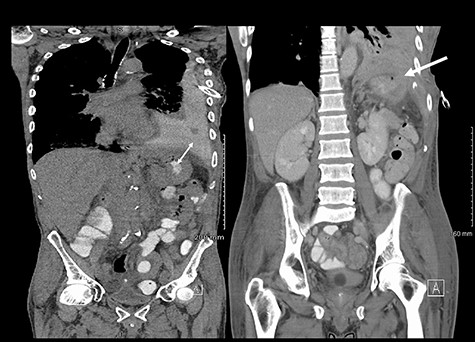

He maintained a high daily chest drain output of between 2.5 and 5 l. Upon recommencement of enteral feeding on day 3, we noticed an increase in opacity of the drainage fluid (Fig. 3). Normal triglyceride and chylomicron levels ruled out a chylothorax. Cultures from the drain eventually grew Enterococcus faecium, Candida albicans and Escherichia coli consistent with gut flora. At this point, an aerodigestive fistula was suspected. This was confirmed by a dye test subsequently performed with green ice cream, which tainted the drainage fluid green (Fig. 4). A repeat CT scan with oral and intravenous contrast delineated a fistula between the greater curvature of the stomach and the left basal pleura, with an extensive empyema (Fig. 5).

(Left) Contrast in stomach and pleural fluid are iso-dense confirming a fistula; (Right) neck of hernia in the diaphragm.